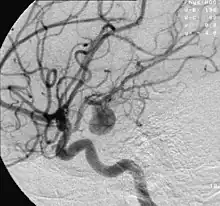

| Circle of Willis Arteries beneath brain | |